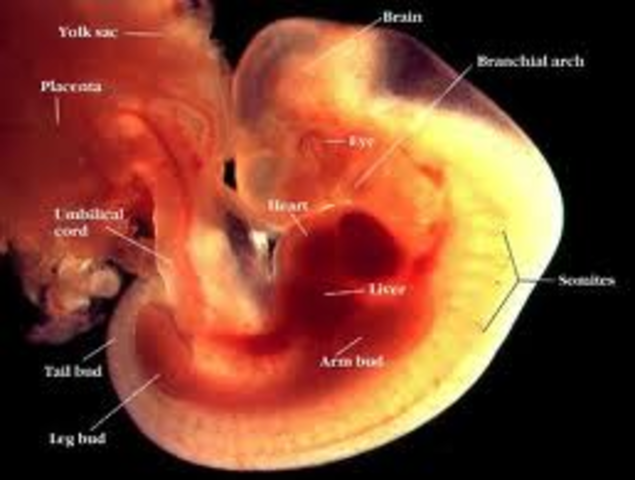

• 7 weeks pregnant

7 weeks pregnant

Hands and feet are emerging from developing arms and legs.Your baby is still considered an embryo and has something of a small tail, which is an extension of her tailbone. Your baby has doubled in size since last week and now measures half an inch long.